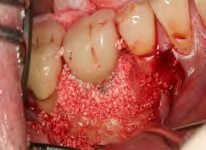

Recently, the literature has cited an approach for successfully managing peri-implantitis that combines mechanical and chemical methods for decontamination that encompasses eight specific steps.36,40,41 These steps include: critically evaluated case selection (Figure 15 through Figure 17); one-flap access (Figure 18); surface decontamination; defect debridement; placement of a biologic on the cleaned implant surface; filling defect with mineralized freeze-dried bone and/or using anorganic bovine bone (Figure 19); coverage with an absorbable membrane or subepithelial connective tissue graft (Figure 20); and coronal positioning of the flap (Figure 21). A subsequent requisite step is professional maintenance (Figure 22).40,41

Fig 18. The patient accepted treatment, and a flap was made. Surface decontamination was achieved without endangering the inferior alveolar nerve.

Figure 18

Fig 19. Biologic bone grafting was performed using a combination of mineralized bone and anorganic bone with a biologic.

Figure 19

Fig 20. A membrane barrier of resorbable collagen was placed buccally, interproximally, and lingually.

Figure 20

Fig 21. The flap was positioned coronally.

Figure 21